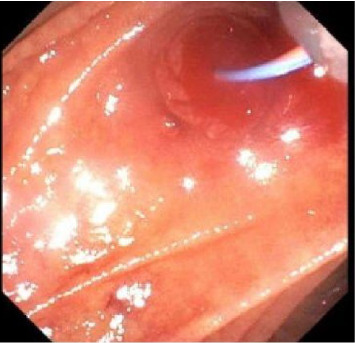

我们提出的情况下,49岁的男子入院急性肝功能衰竭合并血流动力学不稳定的胆道继发出血静脉曲张在胆管。由于静脉出血,放置全覆盖自膨胀裸金属支架(fcems)被认为是该患者肝动脉栓塞的最佳治疗选择。该手术的成功表明,fcems可以被认为是急性肝衰竭并发门静脉高压性胆道病并发血流动力学不稳定胆道患者肝移植的桥梁。

We present the case of a 49-year-old man admitted for acute liver failure complicated by hemodynamically unstable hemobilia secondary to bleeding varices in the bile duct. Placement of a fully covered self-expanding bare metal stent (FCSEMS) was considered the best treatment of choice over hepatic artery embolization in this patient because of the venous source of bleeding. The success of this procedure indicates that FCSEMS can be considered as a bridge to liver transplantation in patients with acute liver failure who develop hemodynamically unstable hemobilia secondary to portal hypertensive biliopathy.